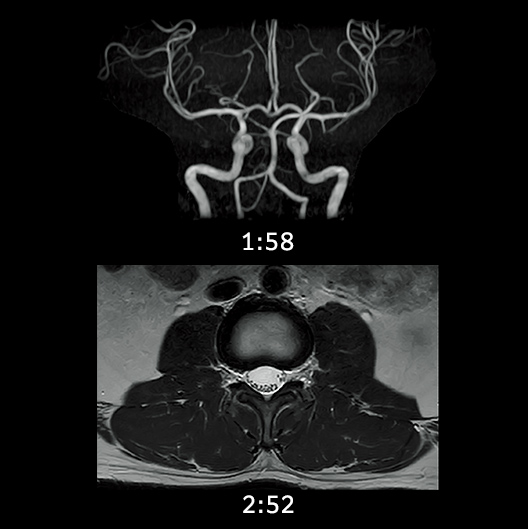

Digital image processing function that automatically creates clipping images of head MRA images.

When AutoExam is executed, clipping is performed automatically after MRA imaging.

It is possible to perform additional clipping on images after automatic clipping.

MRA

without clipping

with AutoClip